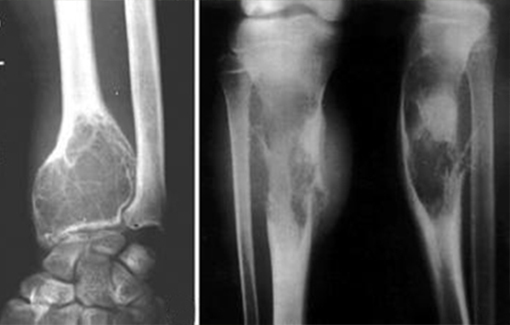

2.肌肉成形术(myoplastic):将相对应的肌瓣互相对端缝合,截骨端被完全覆盖包埋,保持肌肉于正常的生理功能状态,形成圆柱状残肢,可以满足全面接触全面承重假肢接受腔的装配 要求. 膝关节离断是将髌韧带及?绳肌腱与十字韧带相缝合。大腿截肢由于?绳肌和内收肌被切断使髋关节内收和后伸的能力减弱,坐骨包容式的假肢接受腔试图控制股骨在更加生理的 内收位,由负重位拍摄的X线片检查发现假肢接受腔的形状对残肢股骨的位置起不到影响,假肢接受腔不能维持股骨于生 物力学轴线的内收位置,它的动力对线主要是取决于外科技术,需要将内收肌固定在股骨残端的外侧,利用肌肉张力维持股骨于内收位,可以减少在一般经股骨截肢患者所见到的向外侧倾斜步态。肌肉的处理方法是将内收大肌在张力下缝合固 定到截骨残端外侧方钻孔处,将股骨置于内收位,把股四头肌腱缝合固定到截骨残端的后侧方钻孔处,保持髋关节于伸直位,小心不要形成医原性的髋关节屈曲挛缩,再将后方和外侧肌肉与这两组肌肉相缝合,维持股骨于生物力学轴线的内收 位置,这些对假肢功能的发挥和改善行走步态都是非常有利的。